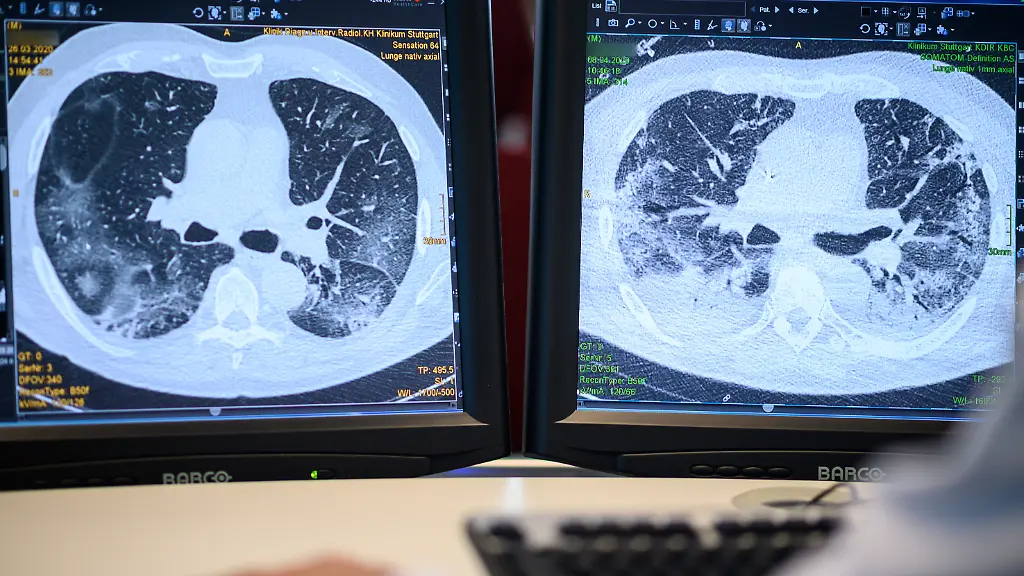

Rolle der LuftverschmutzungWie beeinflusst Feinstaub den Covid-19-Verlauf?

Das Coronavirus greift die Lunge an und auch Feinstaub schädigt sie. Da erscheint naheliegend, dass eine hohe Luftverschmutzung die Todesfall-Rate unter Covid-19-Patienten erhöht. Aber stimmt das? Die Harvard-Universität hat das in einer Studie untersucht.